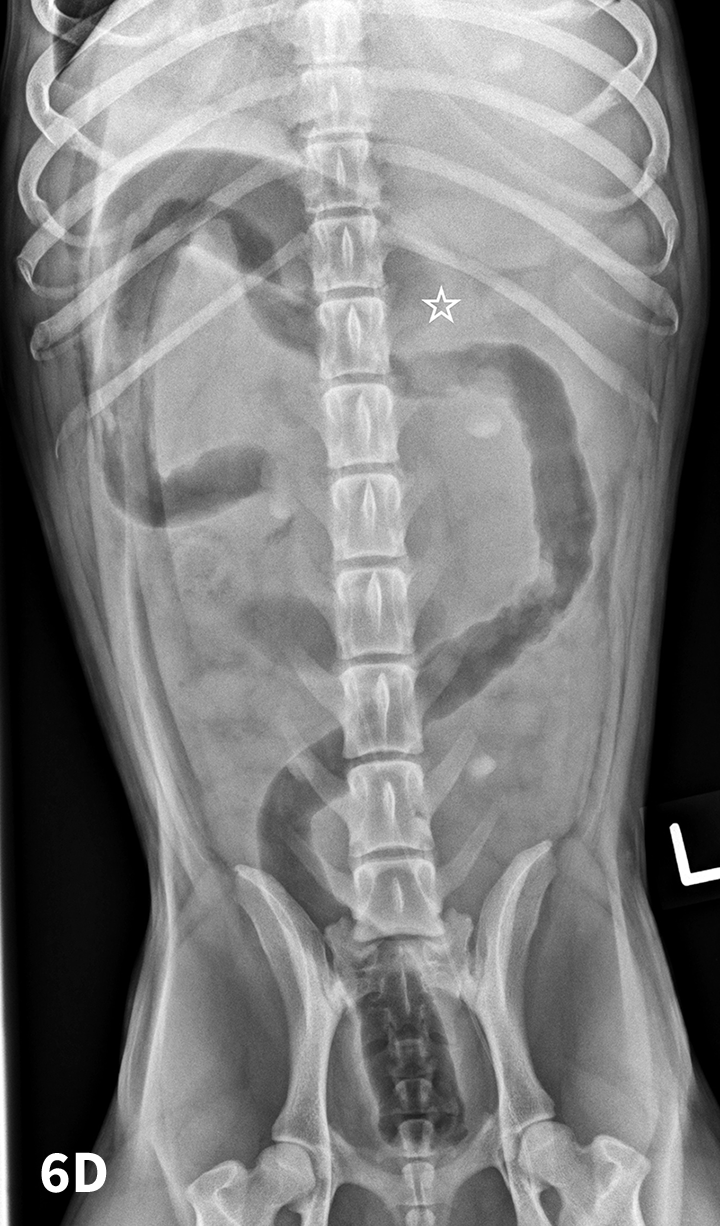

Normal Vd Abdominal Radiograph Dog Gdv Bloat Dog Ray Stomach Radiograph

Normal Vd Abdominal Radiograph Dog Gdv Bloat Dog Ray Stomach Radiograph Vd X Ray Meaning Several different angles are used to assess radiographs. The two that are used the overwhelming majority of time are: A dorsoventral (dv) view indicates the opposite. radiographic positioning terminology is used routinely to describe the position of the patient for taking various radiographs. The lateral (side) view where. radiographic examination of the thoracic cavity has typically consisted of. Vd X Ray Meaning.